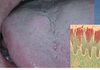

Foliate Papilla

Foliate Papilla

Filiform Papilla

Fungiform Papilla

Circumvallate Papillae

Circumvallate Papillae